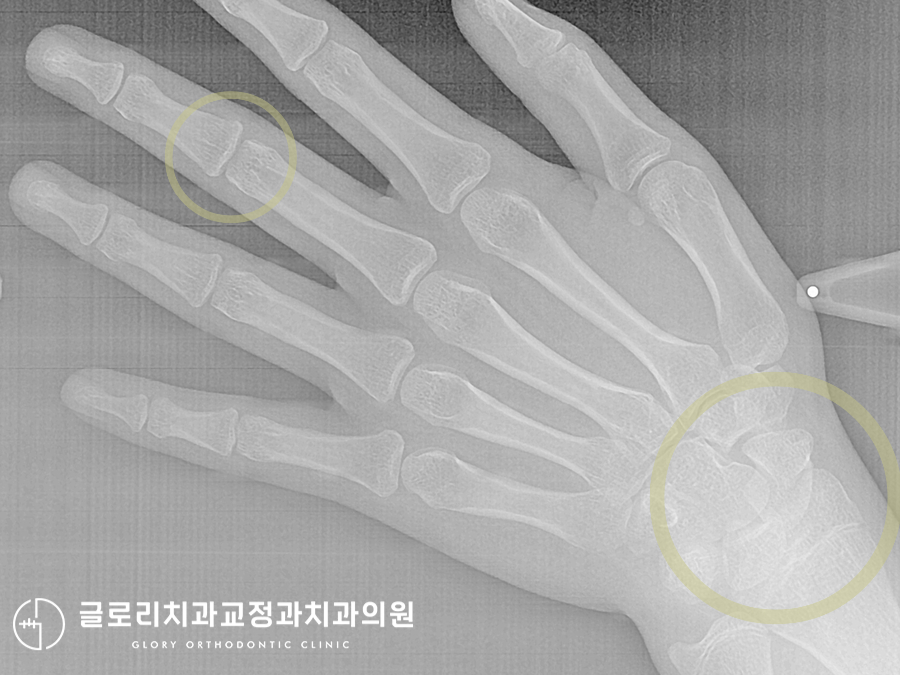

성장 속도를 예측할 수 있는

수완부 방사선 촬영도 진행하여

알맞은 치료 시기가 맞는지

확인하는 과정까지 거쳤습니다.